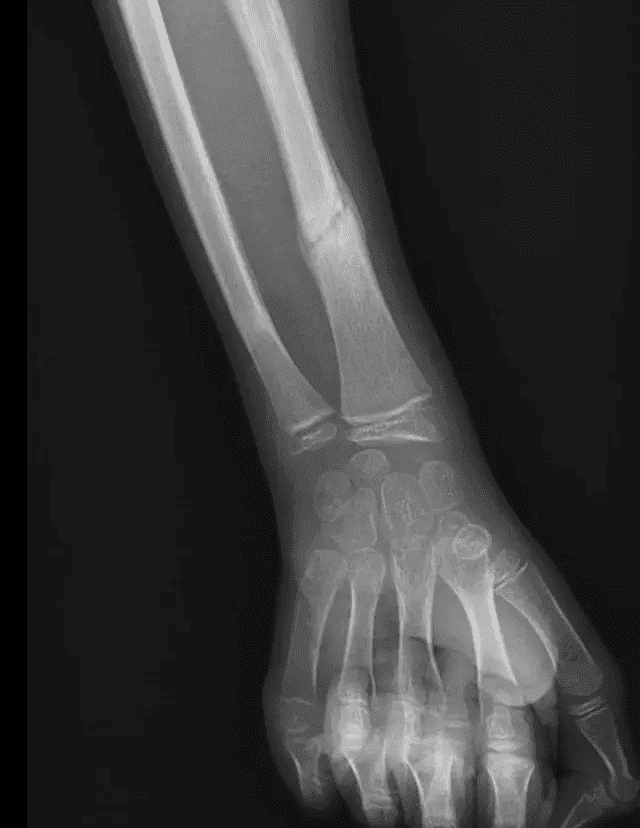

Suivi évolutif de la fracture du radius à 15 jours d'intervalle avec constitution d'un cal osseux à 1 mois sans déplacement secondaire associé.

Suivi à 1 mois